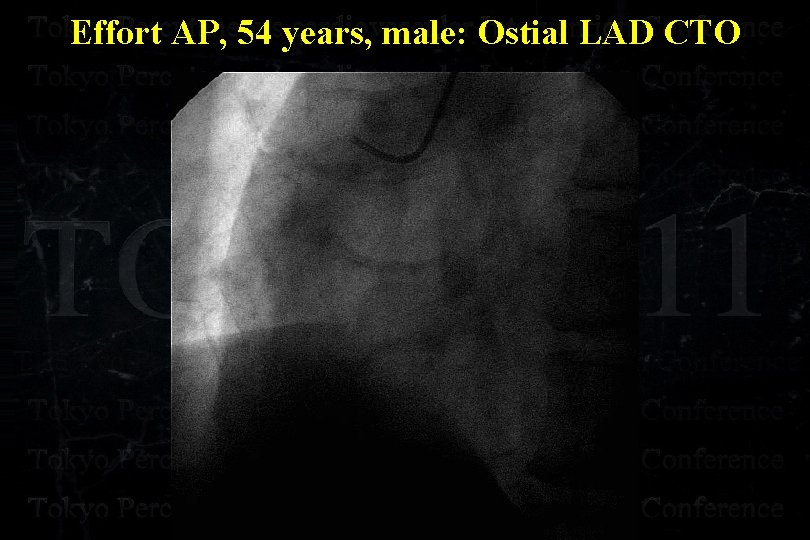

Effort AP, 54 years, male: Ostial LAD CTO

Effort AP, 54 years, male: Ostial LAD CTO

Effort AP, 54 years, male: Ostial LAD CTO

Effort AP, 54 years, male: Ostial LAD CTO

Effort AP, 54 years, male: Ostial LAD CTO

Effort AP, 54 years, male: Ostial LAD CTO

Effort AP, 54 years, male: Ostial LAD CTO Separated Conus Branch !